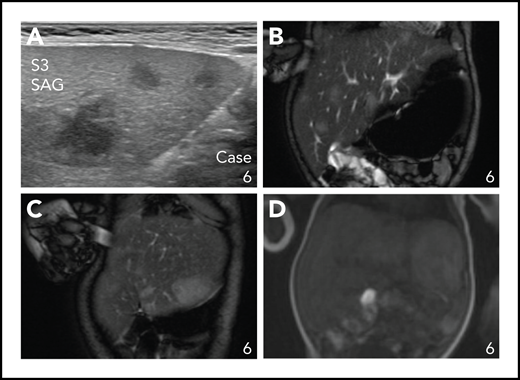

Focal liver lesions in an infant with multisystemic disease with liver and hematopoietic involvement (Group 1A). (A) Ultrasound image showing 3 hypoechoic lesions in liver segment 3. (B-C) Coronal T2-weighted fat-suppressed MRI images showing multiple hyperintense lesions in the liver, including a large rounded lesion in liver segment 3 (C). (D) Coronal T2-weighted contrast-enhanced MRI image showing late contrast accumulation in the large rounded lesion in liver segment 3.

Patients in Group 1A ranged from 0 days to 5 months of age and presented with hepatomegaly, anemia, and thrombocytopenia. In addition, 5/6 had splenomegaly, 5/6 displayed leukocytosis, and some had measurable liver dysfunction, such as elevated liver enzymes, high bilirubin, and/or decreased serum protein and albumin levels. In 3 cases, focal lesions were seen in the liver (Figure 2). Coagulation profiles were available for 4/6 patients (supplemental Table 2), revealing prolonged prothrombin time, activated partial thromboplastin time, and decreased serum fibrinogen in Case 3. Small numbers of ALK+ histiocytes were observed in the bone marrow of all 5 patients that had a bone marrow biopsy performed. Regarding additional sites of disease, 2/6 had renal involvement,31 1/6 had interstitial lung involvement requiring prolonged oxygen supplementation,47 and 1/6 had skin involvement (Table 3).